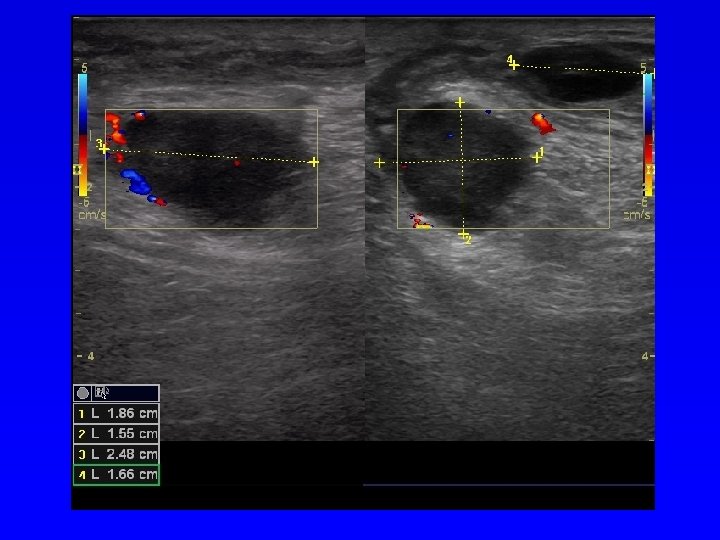

Ultrasonografie Podle echogenity (odrazivosti) lze uspořádat tkáně: Kost (výrazně echogenní), vazivo, sval, tuk, chrupavka, tekutina (minimální echogenita). Anechogenní struktura- černá Hypoechogenní struktura- šedá Hyperechogenní - bílá Diagnostika měkkých tkání Diagnostika nádorů Diagnostika VDK Zjištění výpotku v kloubu Další využití